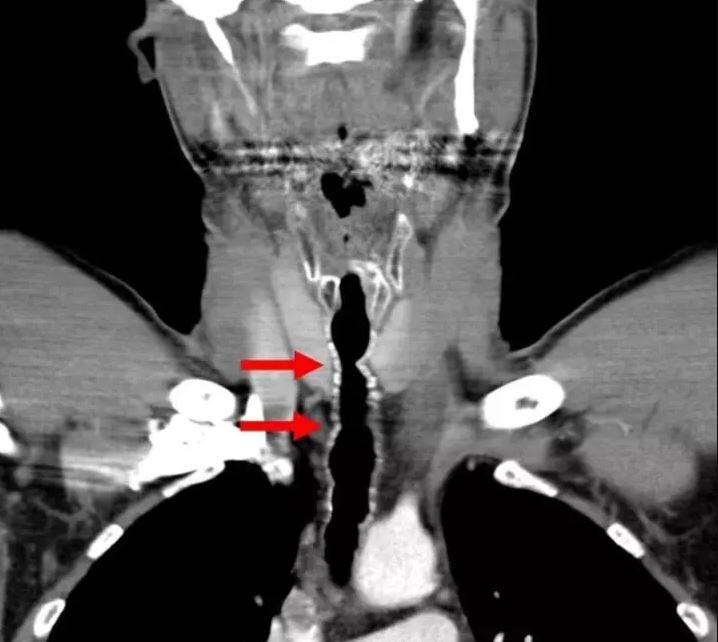

Uzun yıllardır sigara kullanan bir adamın boğazının arka kısmında siyah, tel gibi kıllar çıkarken, adama endotrakeal kıllanma adı verilen son derece nadir bir teşhis konuldu. Avusturyalı bilim insanları, sigaranın boğaz iltihabını tetikleyebileceğini ve bunun da hücrelerin kıl köklerine dönüşmesine neden olabileceğini söyledi.

Uzun yıllardır sigara kullanan bir adamın boğazının arka kısmında siyah, tel gibi kıllar çıkarken, adama endotrakeal kıllanma adı verilen son derece nadir bir teşhis konuldu.

Sigaranın insan sağlığı üzerinde birçok zararı bulunurken, Avusturyalı bir adamın yaşadığı olay herkeste şok etkisi yarattı. 52 yaşındaki bir kişi; ses kısıklığı, nefes almada zorluk ve kronik öksürük şikayetleriyle hastaneye başvurdu.

Avusturyalı hasta, 1990 yılında 20 yaşındayken sigara içmeye başladığını ve bir keresinde saçından bir kıl çıktığını iddia ederken, hastanın solunum yollarına küçük bir kamera göndererek inceleme yapıldı.

Doktorlar, adamın boğazında birkaç koyu renkli kıl çıktığını keşfederken, tüyleri almayı başardılar ve geçici bir rahatlama sağladılar.